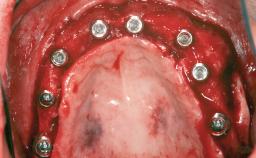

Shell Technique for Horizontal and Vertical Maxillary Bone Augmentation in a Partially Edentulous Patient with Aggressive Periodontal Disease

# of Implants 3

Type of Implants One-Piece

Bone Augmentation Horizontal|Staged|Vertical

Augmentation Materials Autogenous chips|Autogenous block(s)|Xenogenous